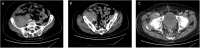

Presentation of case: The patient is an 83-year-old male who presents with severe sepsis, right lower quadrant and right leg pain. Additional past medical history is significant for rectal cancer status post resection and radiation therapy in 1997. Computed tomography (CT) on admission revealed a right iliopsoas muscle abscess, an inflamed Appendix and a pseudo aneurysm arising from the right external iliac artery. After consultations by multiple specialties, the plan was to proceed with percutaneous drainage of the abscess, antibiotic therapy and subsequent repair of the pseudoaneurysm. CT guided drainage of the iliopsoas abscess was performed with return of hemorrhagic fluid. Due to the concern of contained pseudoaneurysm rupture, the patient was taken for expedited repair. Due to the patient's frailty and hostile abdomen, we performed embolization of the right external iliac artery pseudoaneurysm with Amplatzer I plugs (St. Jude Medical, St. Paul MN) and left common femoral to right superficial femoral bypass with cryopreserved cadaveric femoral vein. Following pseudoaneurysm exclusion, continued percutaneous drainage and antibiotic therapy, the patient has done well with no further evidence of infection.